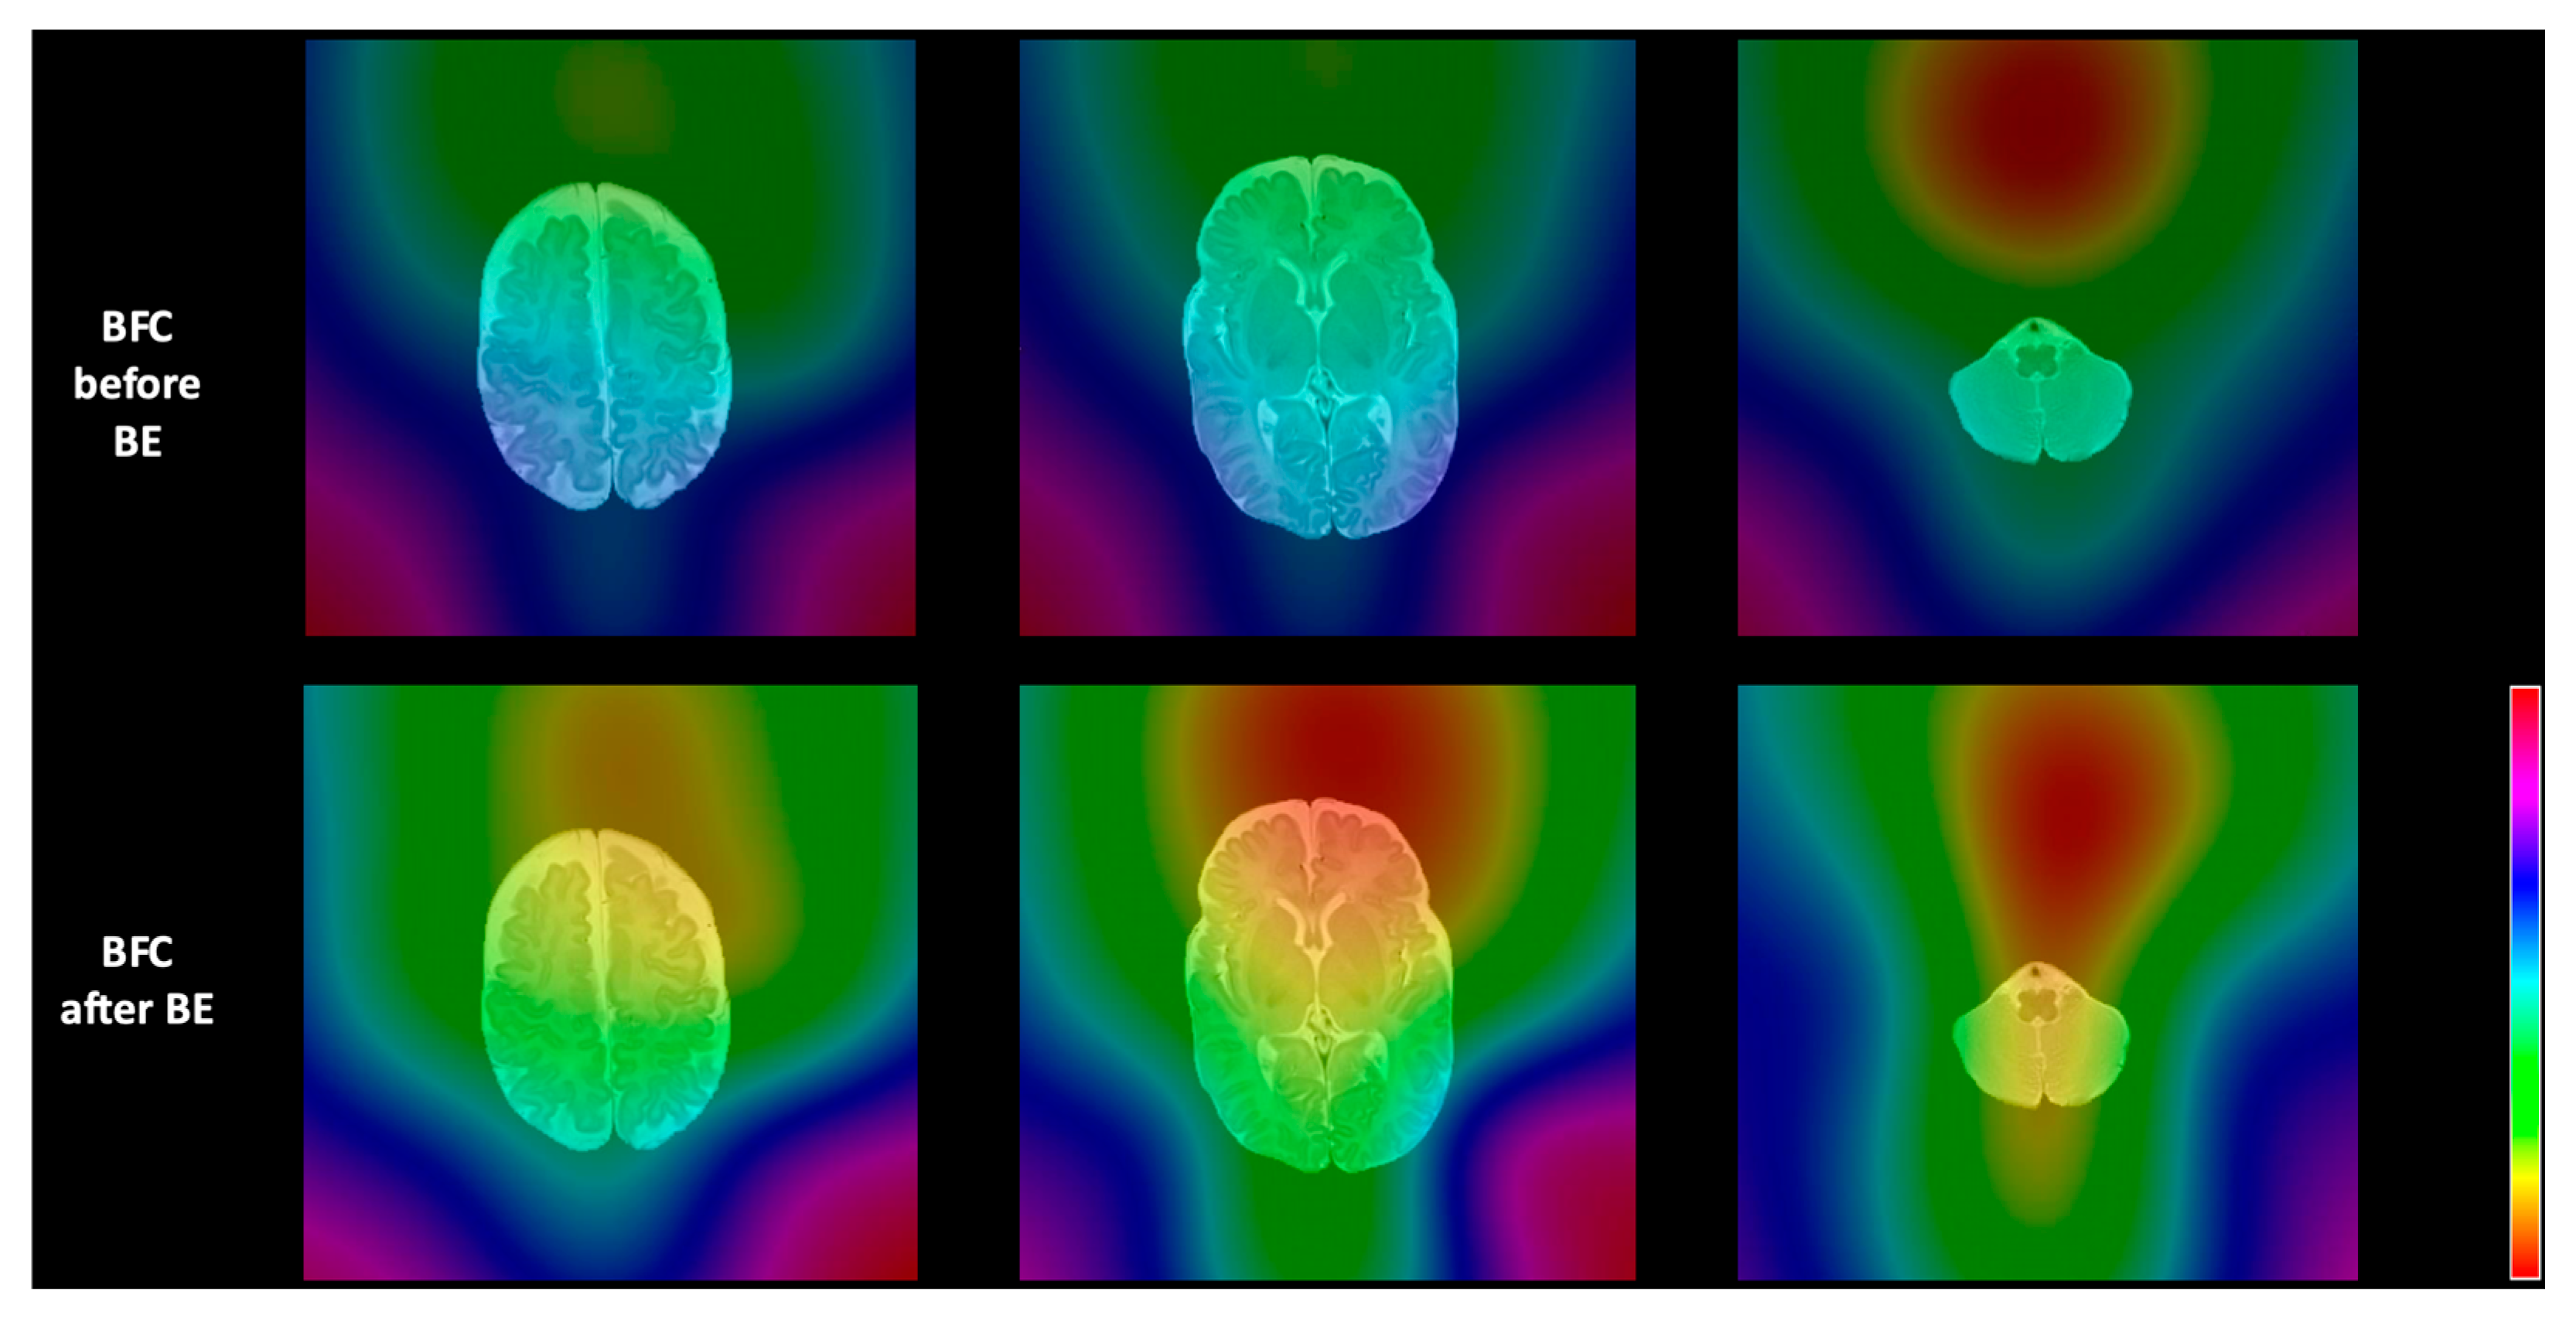

2.3.2. Bias Field Correction Methods

3.1. Assessment of Intensity Variability and Segmentation Performance